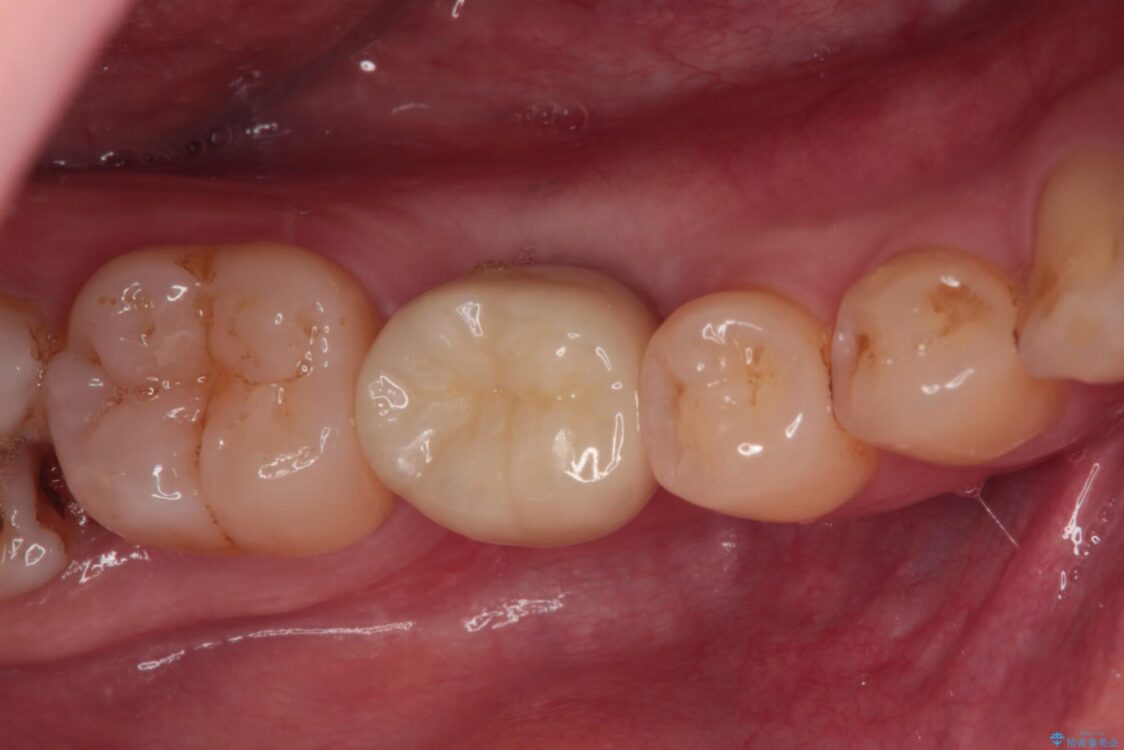

治療後

• 空いている時間を利用して通院 奥歯のインプラント治療 治療後画像